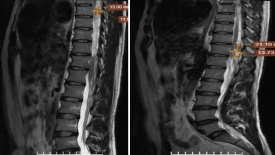

Đau thắt lưng tưởng đơn giản, phát hiện nhiều khối u trong ống đốt sống

Đau thắt lưng kéo dài, đặc biệt khi xuất hiện về đêm hoặc tăng khi thay đổi tư thế, có thể là dấu hiệu cảnh báo những tổn thương tiềm ẩn trong cột sống, trong đó có các khối u bao dây thần kinh.